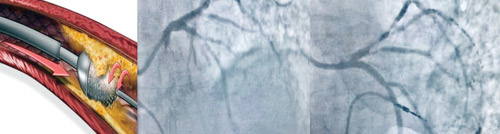

من جهته قال د. مبارك الغامدي المدير الطبي للمستشفى أن كفاءة الفريق الطبي وحرفيته العالية بالإضافة، إلى التجهيزات الطبية المتقدمة ساهم في نجاح العملية، مشيراً إلى جهاز «RotaPro» الذي تم تزويد مركز القلب بمستشفى د. سليمان الحبيب بالسويدي به مؤخراً، يعد التقنية الأحدث عالمياً في علاج انسدادات الشرايين بفعالية كبيرة وأمان عال، حيث يعمل بالثاقب الماسي الذي يدور بسرعة عالية لتفكيك التكلس وفتح الشرايين، دون الحاجة إلى الجراحة وبالتخدير الموضعي، وهو الأمر الذي يقلل من مخاطر الاختلاطات والمضاعفات الطبية، والنزيف، وكذلك يتطلب فترة تنويم ومتابعة طبية أقل.